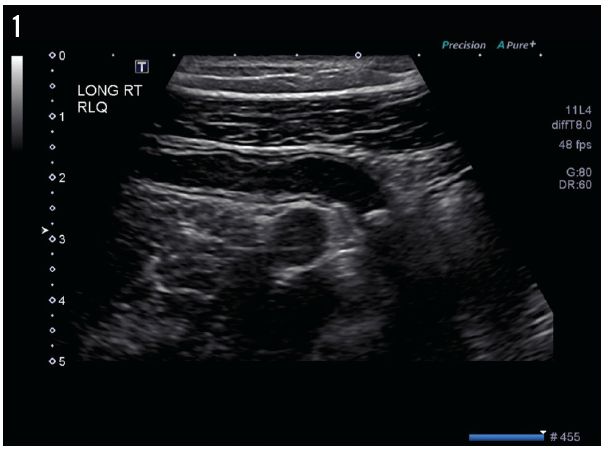

Jeffrey W. Taub, MD; Muhammad Ubaidulhaq, MD; Samie Ullah Ahmed, MD

A 17-year-old African American boy with sickle cell disease was admitted to the emergency department with a 4-day history of sharp, stabbing abdominal pain and lower back pain.